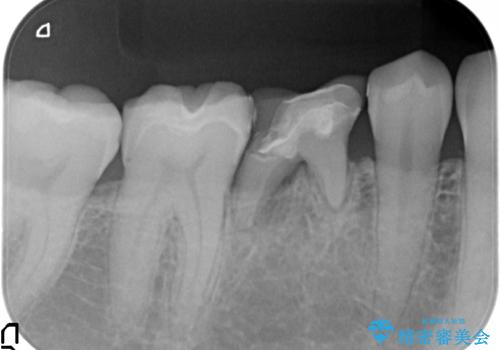

- 大人になっても残っていた乳歯が噛むと痛くなり、治療を求めて来院されました。

残す手段を検討しましたが大きな虫歯・根尖病変の存在し、大きく歯ぐきも腫れ炎症も強く認められる状態を改善するため抜歯を行いインプラントによる咬合機能回復を計画します。

大人になっても残っている乳歯は根管治療や他の治療で残せる場合もありますが、今回のように状態が悪い場合早期に抜歯をすることで歯槽骨が温存でき十分に安定した骨量でインプラントによる機能回復を達成することができました。